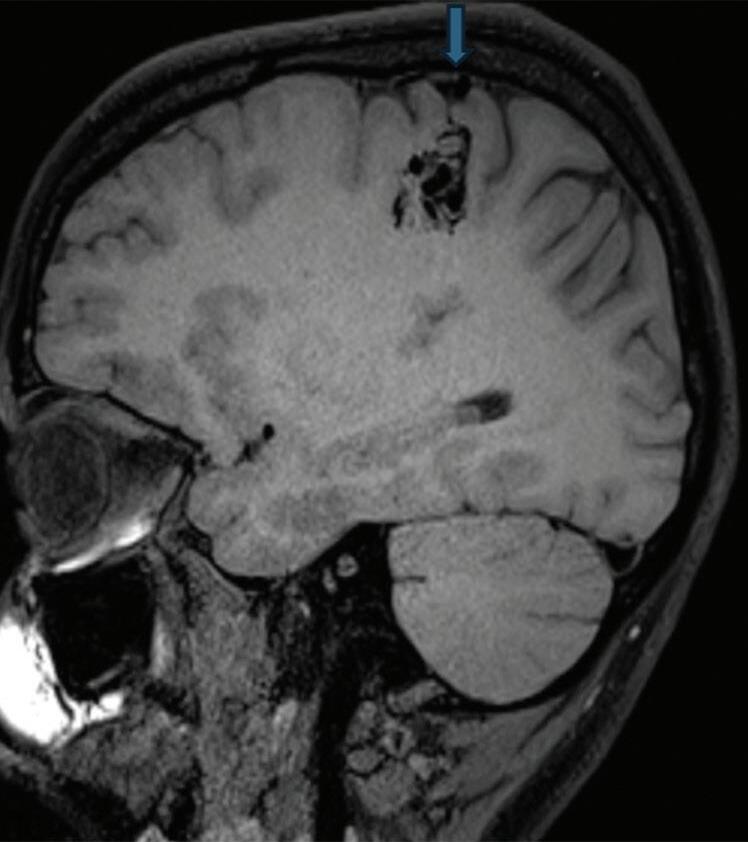

Fig. 1-8. (a-c) RNM T1 com contraste, cortes sagital (a), coronal (b) e axial (c) demonstrando MAV não rota com nidus localizado no lobo occipital à esquerda (setas longas). (d) Arteriografia digital cerebral com injeção de contraste via carótida direita (AP) mostrando a contribuição da carótida direita na irrigação da MAV contralateral. (e,f) Com injeção de contraste via carótida esquerda, em Perfil e AP respectivamente, observa-se nidus compacto nutrido por ramos da artéria cerebral média à esquerda e a veia de drenagem precoce se dirigindo para o seio sagital superior. Projeções em AP (g) e em perfil (h) demonstrando a contribuição do sistema vertebrobasilar por meio de ramos distais da artéria cerebral posterior à esquerda e drenagem para os seios sagital superior e sigmoide à esquerda (setas curtas).